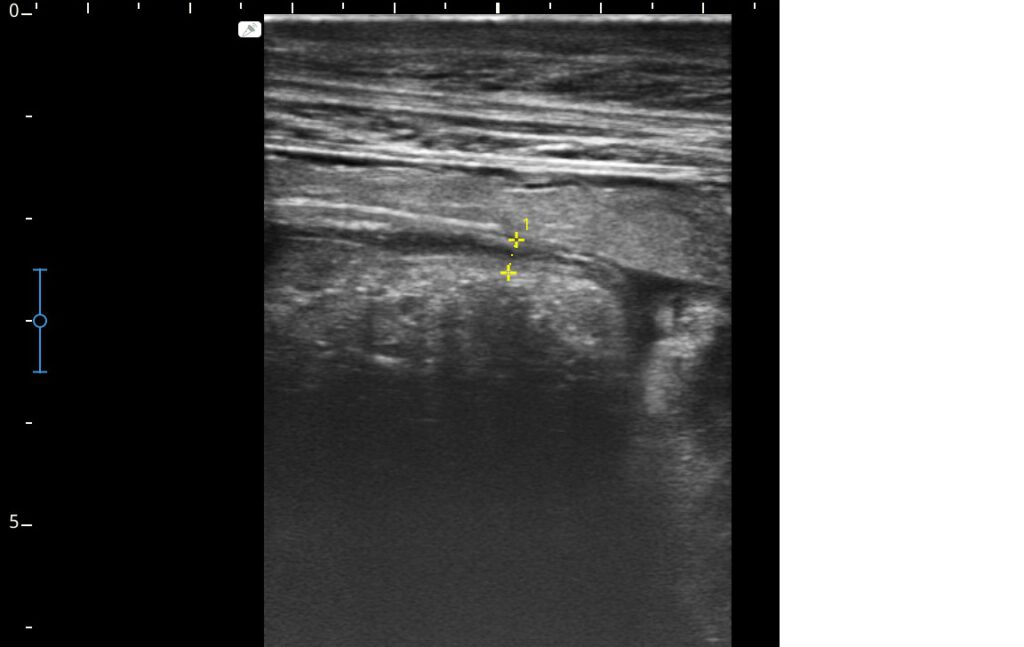

Orthopädie

Bildgebende Verfahren:

Ultraschall, Röntgen, JETZT auch Endoskopie